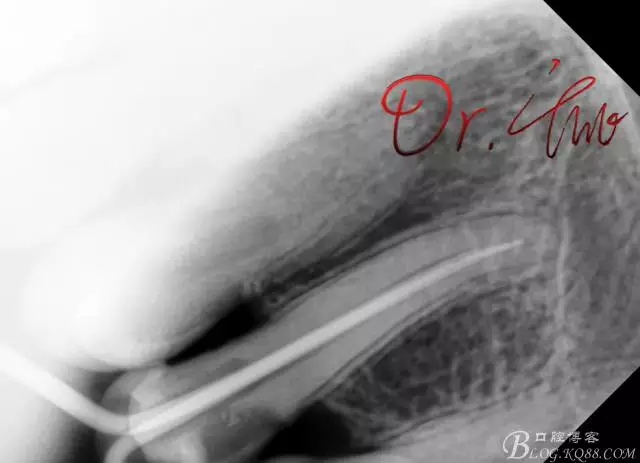

拍片確定長度

640.webp (1).jpg